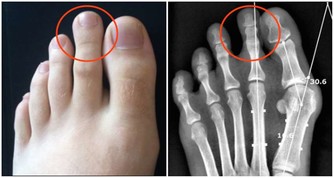

2、各種骨骼疾病

鈣缺乏很容易導致骨骼疾病和兒童。如果缺鈣會導致佝僂病,雞胸,缺鈣的孩子會出現生長痛,如果成人缺鈣會導致腰酸背痛、骨質增生。退行性病變,老年人缺鈣就會導致骨質疏鬆,容易骨折。很多老年人因為缺鈣,50以上就會出現駝背,還有一些人因為缺鈣,導致股骨頭壞死。